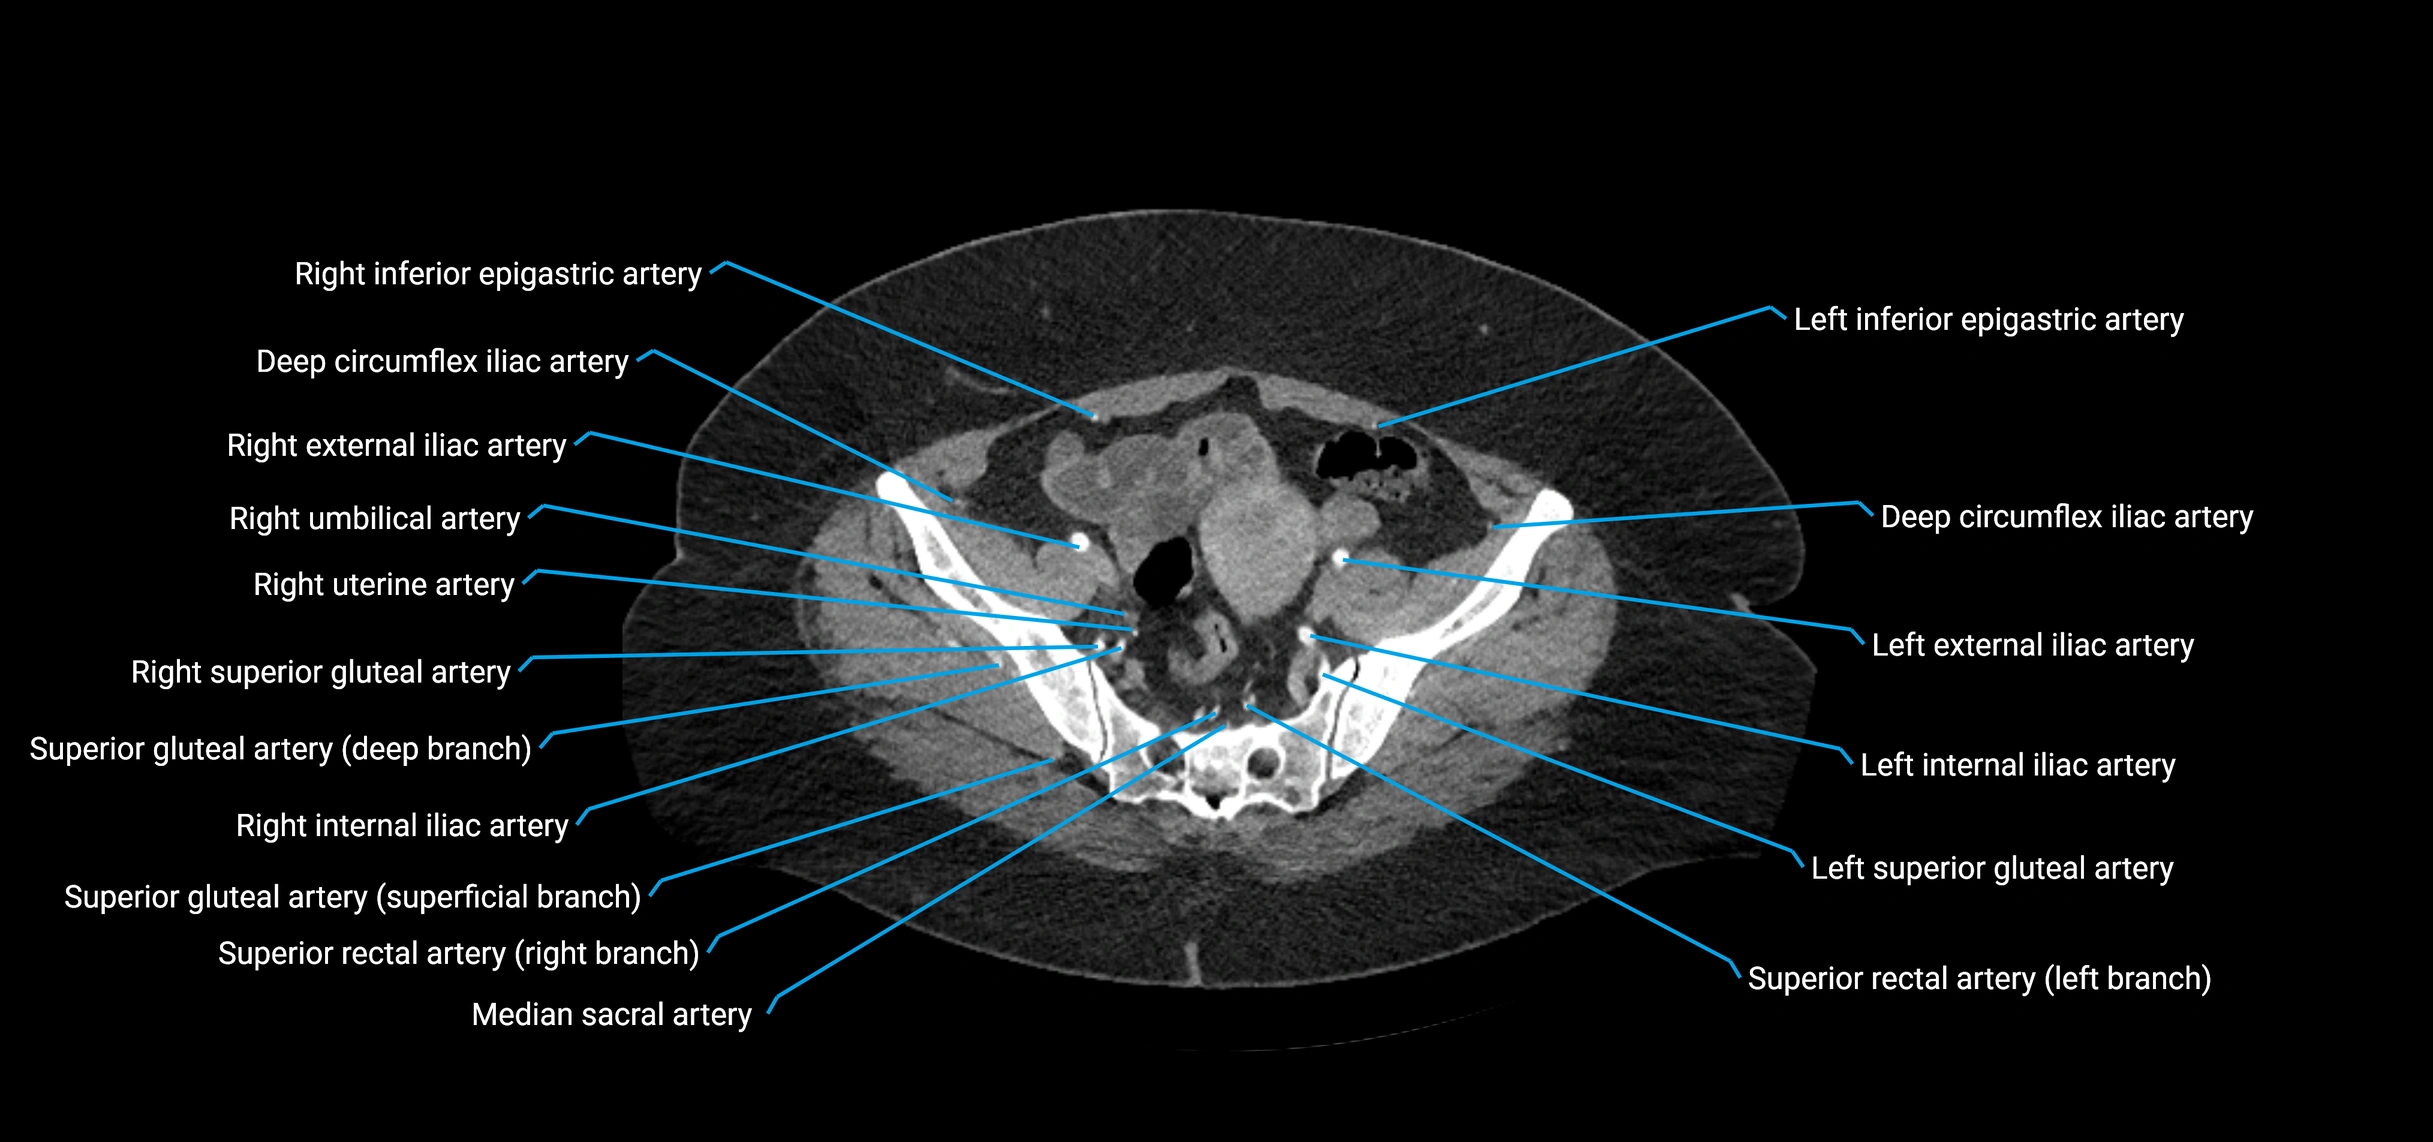

Contrast-enhanced CT (CTA):

• Gold standard for abdominal aortic imaging

• Provides excellent detail of lumen, wall, aneurysm, thrombus, and branch vessels

• Multiplanar and 3D reconstructions help in aneurysm measurement, stent graft planning, and dissection evaluation